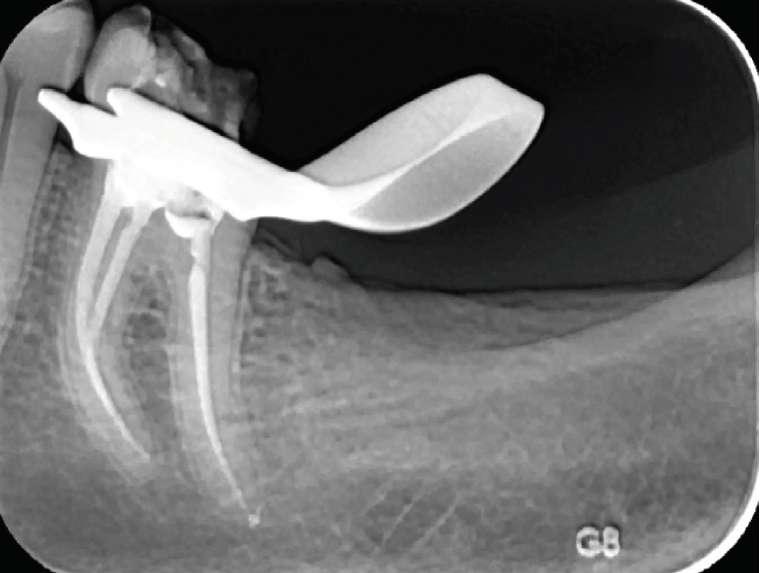

Wenn man sich dieses präoperative Röntgenbild ansieht, sind zwei Hinweise zu diesem endodontischen Fall zu erkennen (Abb. 1): Obliteration der Pulpakammer und enge Kanäle Ungewöhnliche Anatomie der distalen Wurzel

FALLBERICHT: Abb.1 Abb.2

Der Verdacht des Klinikers auf eine ungewöhnliche Anatomie der distalen Wurzel wurde durch das abgewinkelte Röntgenbild bestätigt, das eine abrupte versteckte Krümmung im apikalen Drittel des Kanals zeigte. Trotzdem ermöglichte der Crown-Down-Ansatz (zunächst Aufbereitung des koronalen und mittleren Teils, wodurch koronale Interferenzen reduziert werden) und die richtige Auswahl sehr flexibler und widerstandsfähiger